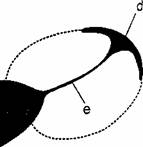

Fig. : Stenoza hipertrofica de pilor. Prezentare schematica a imaginii radiologice. . Se evidentiaza: imaginea de 'cioc' corespunzatoare inceputului canalului piloric (b); imaginea amprenta lasata pe antrul piloric de 'tumora' (c); amprenta lasata pe bulbul duodenal de 'tumora pilorica (d); canalul piloric alungit si filiform ( imaginea in "negativ" a tumorii pilorice (a).